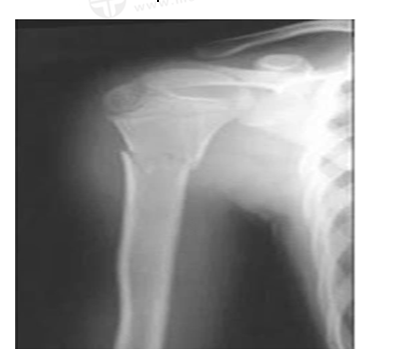

男,45岁,摔伤40分钟,诊断为

A.右尺骨骨折

B.右桡骨骨折

C.右肱骨骨折

D.左肱骨骨折

E.右肱骨骨质疏松

【答案】C